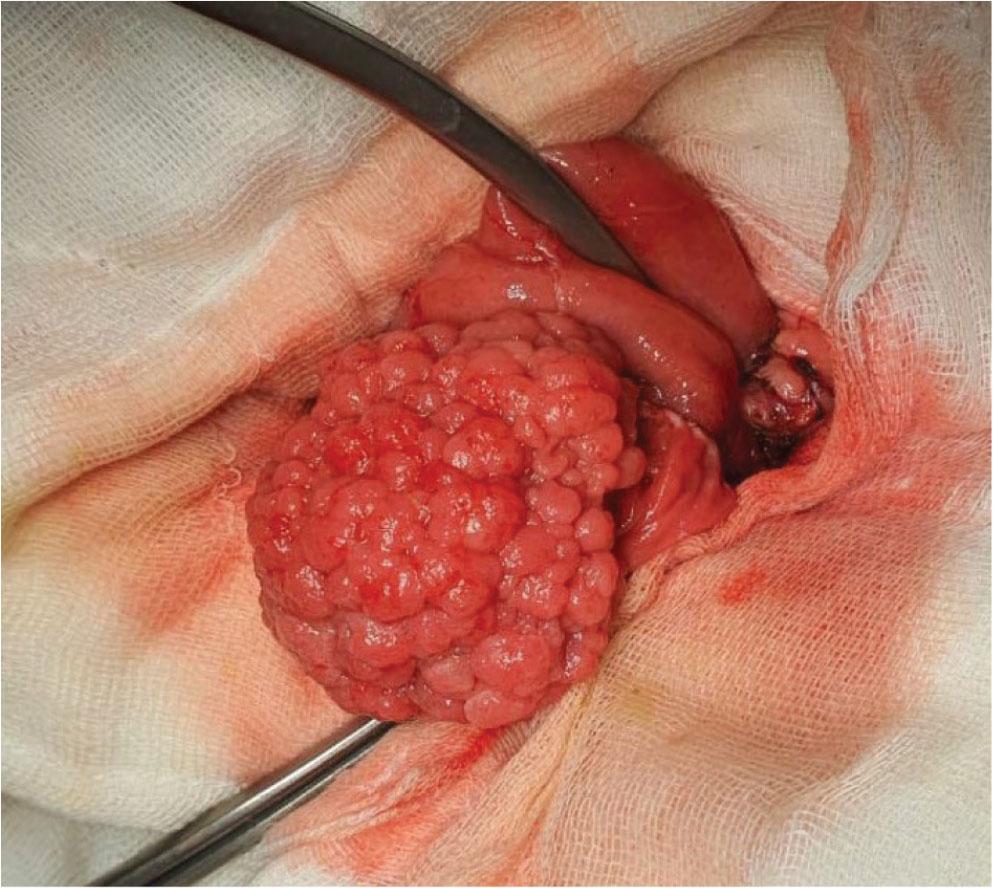

Figure 2.